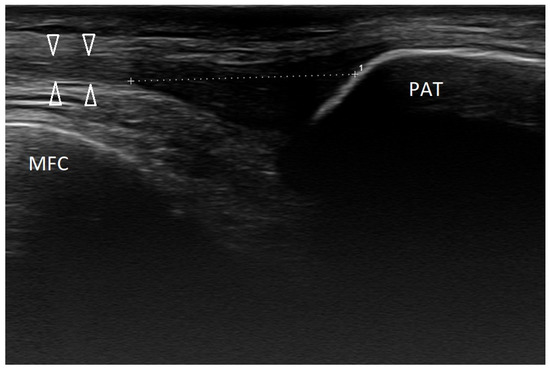

3.2.2. Osgood–Schlatter Disease

3.2.3. Ligament Injuries